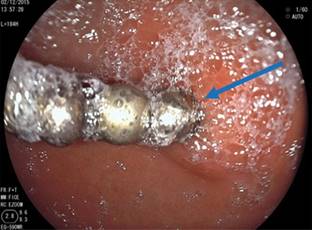

Se realiza endoscopía alta con equipo rígido en el que se aprecian tres imanes en la faringe que se extraen con pinza de caimán. Posteriormente, se efectúa panendoscopía, donde se observa esófago sin alteraciones. En estómago, a nivel del antro, se observaron ocho imanes que se extraen con red atrapa pólipos (Figura 3). Se identifica una úlcera de 4 mm con bordes congestivos y edematosos, en su interior se encuentra un imán incrustado (Figura 4). En el duodeno no se identifican lesiones.